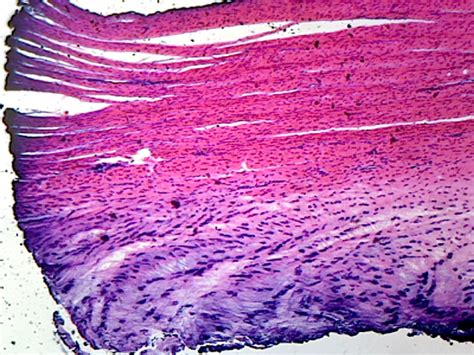

Structure of Fibrocartilage Under a Microscope

When viewed under a microscope, fibrocartilage exhibits a distinct structure that sets it apart from other types of cartilage. The key components of fibrocartilage include:

• Collagen Fibers: These fibers are densely packed and arranged in a parallel or woven pattern, providing tensile strength and resistance to deformation.

• Chondrocytes: These are the cells responsible for producing and maintaining the cartilaginous matrix. In fibrocartilage, chondrocytes are fewer in number compared to hyaline cartilage but are essential for tissue repair and maintenance.

• Ground Substance: This is a gel-like matrix composed of proteoglycans and glycoproteins, which helps to distribute mechanical loads and maintain the tissue's hydration.

Under a microscope, the dense collagen fibers appear as thick, wavy strands that crisscross each other, creating a robust framework. The chondrocytes are scattered throughout this matrix, often appearing as small, rounded cells with a distinct nucleus. The ground substance, although not visible under standard light microscopy, can be inferred from the overall appearance of the tissue.